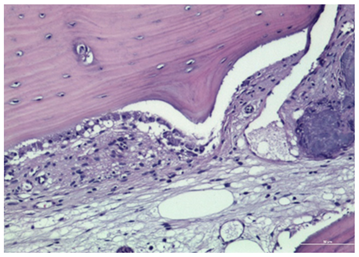

3.2. Histological Observation